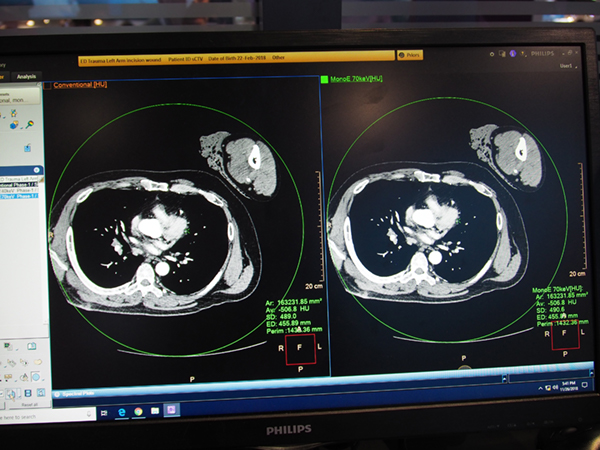

Philips(フィリップス)のCTは,スペクトラルCT装置「IQon Elite Spectral CT」の臨床画像を中心に展示を行った。今回は装置のモックアップは設置せず,モニタにて装置の特徴や技術について説明が行われた。

IQonシリーズは,上下2層の検出器を搭載し,高エネルギーと低エネルギーのデータを分けて収集することで,レトロスペクティブにスペクトラルイメージング解析ができるCTシステム。IQon Elite Spectral CTでは,画像再構成ユニット“HyperSight Elite Spectral Reconstructor”により画像処理速度が向上し,真にすべてのルーチン検査のスペクトラルイメージングが可能になった。実際に,日本国内のユーザーも日常的にスペクトラルイメージングを実施しており,それは大学病院に限らず,1台体制でMRI検査を行っている一般病院も同様だという。さまざまな領域を対象に,日常的にDual Energyができることで,各施設で多彩な検討が進められており,その成果としてRSNA 2018ではIQonシリーズを使用した演題が日本から5題採択されている。展示では,日本国内のユーザーの画像も多く紹介された。